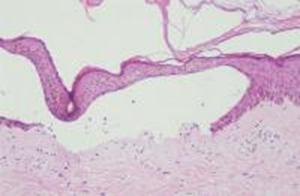

Foto 6 : PCT: Bula subepidermica, membrana bazala festonata, hialinizarea vaselor de sange, elastoza solara, corpusculi intracelulari "in senila". |